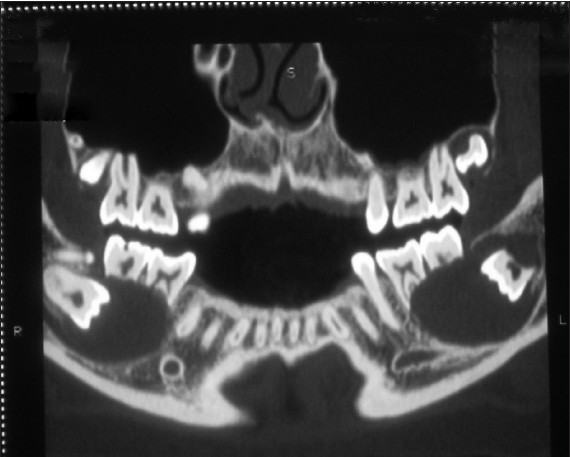

A radiographic investigation by CT scan revealed a unilocular well-defined corticated hypodense lesion involving impacted mandibular third molars bilaterally [Figure 3]. The dimensions of the hypodensities were 31 and 42 mm anteroposteriorly on the right and left, respectively. There were also associated supernumerary teeth on both sides. The supernumerary teeth were small in size than third molars with single conical root and were placed coronally in close relation to third molars on both sides. The hypodensities were associated with radicular resorption of the first and second molars. Radiographs also revealed the inferior displacement of the mandibular canal. Incidentally another bilateral hypodense lesion associated with the crowns of maxillary third molars was observed. CT-Scan revealed a well-defined and corticated margin was observed surrounding the unilocular hypodensity. In maxilla, CT-scan revealed the dimensions of hypodensities around the crowns of third molars to be 15 and 18 mm in diameter on the right and left side, respectively [Figure 4] and [Figure 5]. There was no root resorption of adjacent teeth observed in maxilla. In all four quadrants the hypodense lesions were attached to the cementoenamel junction of the third molars at an acute angle which is one of the classical radiographic finding in cases of dentigerous cyst. Coronal sections and three-dimensional CT revealed bilateral lingual and buccal cortical perforations in mandible [Figure 6]. On aspiration a straw-colored fluid was obtained from each of these cystic lesions which is diagnostic of a dentigerous cyst [Figure 7]. | Figure 3: CT image showing bilateral expansile radiolucent lesion surrounding both the mandibular and maxillary third molar regions along with supernumerary teeth

Click here to view |